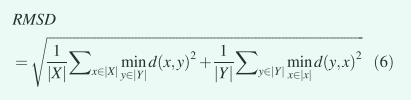

残差均方偏差计算分割轮廓和手动轮廓之间的残差均方距离。 RMSD 计算为